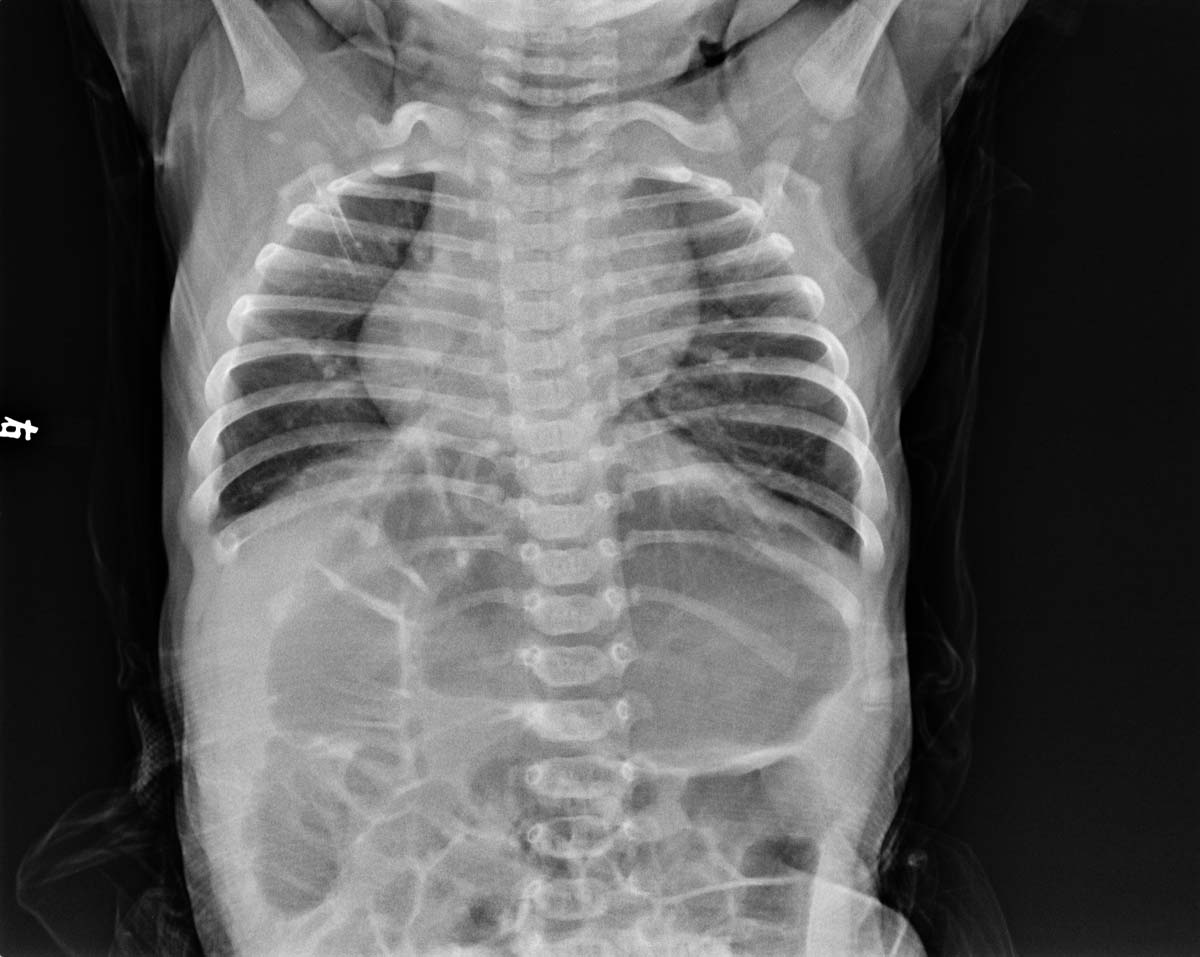

男,21天,片号码没错,又结合透视与片上所见相同,请教能否诊断右位心?

右旋心   心尖指向右,而其他内脏不转位,胃泡、肝脾均在正常位置,称为右旋心。必要时加做超声检查,进一步确定肝脾位置可证实。